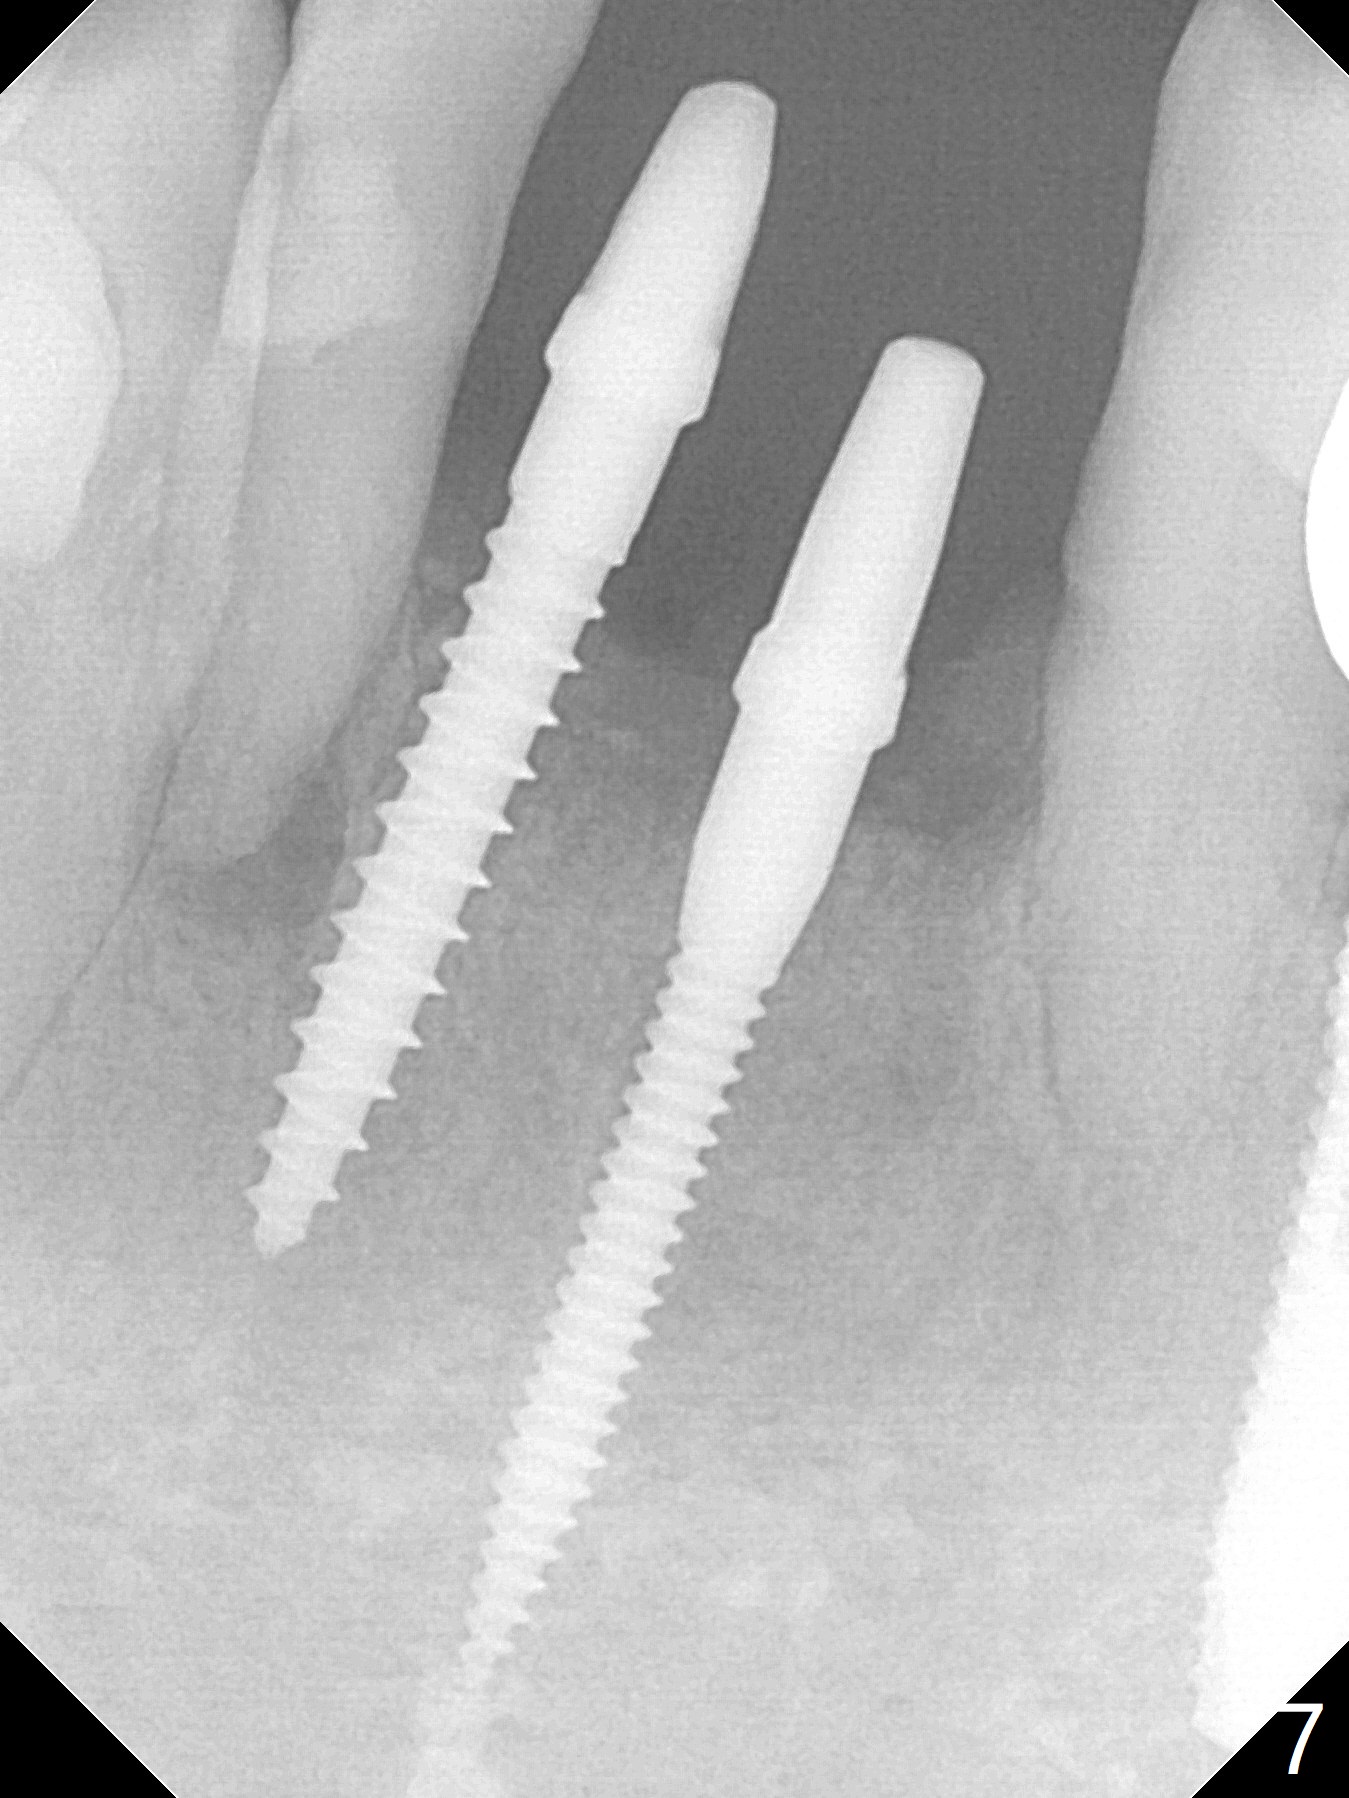

Two and a half months after loss of a 2 mm 1-piece approximately at #23 (Fig.1,2), it appears that the site of #24 (Fig.3 line) is more appropriate because the bone is higher. After removal of the pointed ridge top, osteotomy is initiated with 1.2 mm drill, followed by 1.5 mm one (Fig.4,5). When the 1.5 mm drill is removed, the new osteotomy (Fig.6 *) is mesial to the old one (^). Since the ridge is narrow (Fig.5,6), a 2x14(4) mm 1-piece implant is placed with GBR (Fig.7). Due to overprep, the torque is 20 Ncm. No immediate provisional is fabricated. Instead periodontal dressing is applied around these 2 implants. Two separate provisionals are fabricated when the wound heals. The one at #24 does not stay. The implant at #24 appears to osteointegrate 6.5 months postop (Fig.8). When the crowns are cemented, the margin is supragingival (Fig.9,10). Water Pik is recommended.